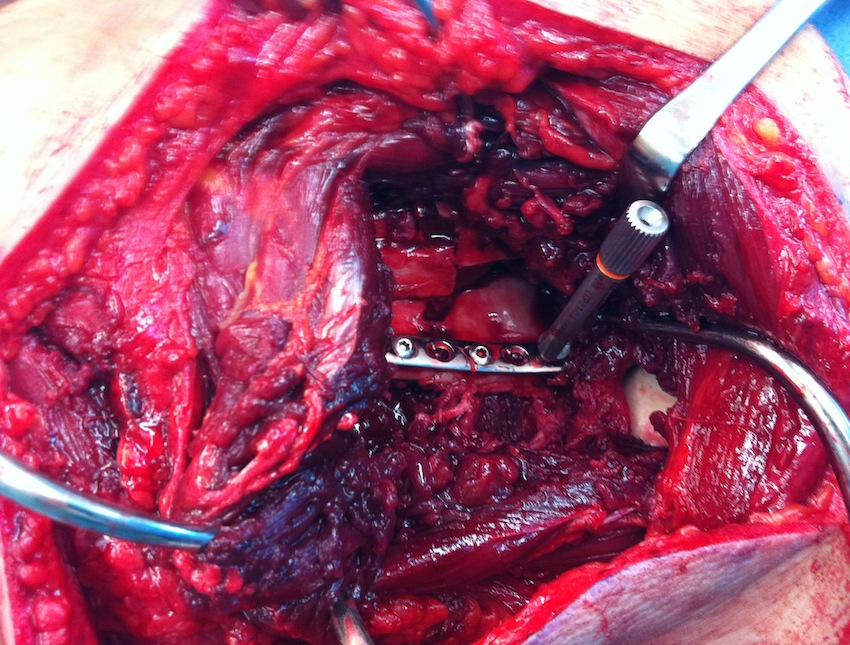

Case 1

- > 1 cm medial displacement

- ORIF via posterior / modified Judet approach

Case 2